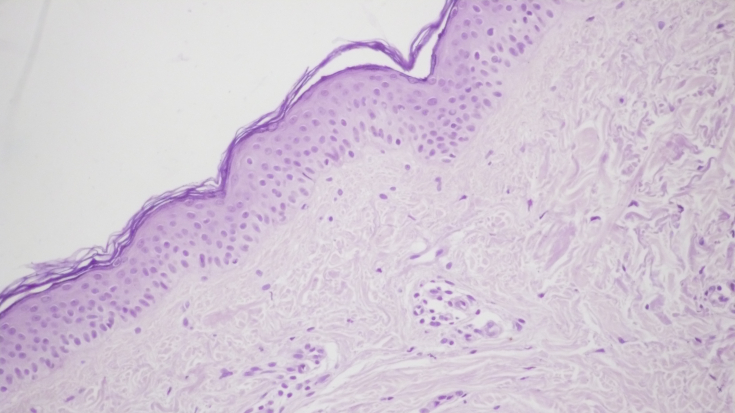

У шкірі пацієнта після монотерапії пептидним препаратом спостерігалося значне зниження запальної інфільтрації (мал. 2а, b). Спостерігалася незначна, переважно периваскулярна лімфоїдна інфільтрація клітин, рідше з'являлися окремі комплекси запальних елементів, розташовані біля придатків шкіри.

Мал. 2. Морфологічна картина шкіри після введення пептидного препарату: запальна інфільтрація дерми виражена набагато менше, х200; в дермі дрібні капіляри зі слабкою периваскулярною лімфоїдно-клітинною інфільтрацією, х200.